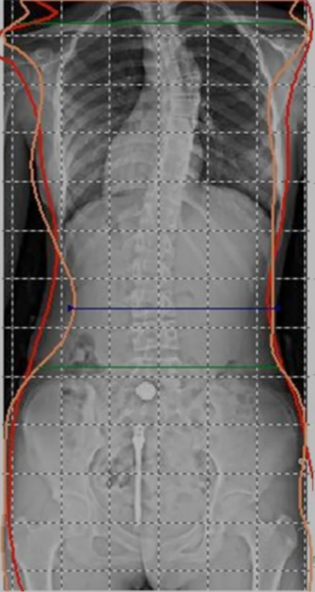

經(jīng)商國家衛(wèi)生健康委現(xiàn)答復(fù)如下: 脊柱側(cè)彎屬于脊柱彎曲異常的一種,是危害兒童青少年健康的常見疾病之一。嚴(yán)重者會(huì)損 傷脊髓和神經(jīng)根,甚至造成癱瘓、心肺功能障礙和其他器官系統(tǒng)疾病。兒童青少年脊柱彎 曲異常直接影響學(xué)習(xí)、生活和就業(yè),影響到國家人才培養(yǎng)的質(zhì)量。

將脊柱彎曲異常納入學(xué)生常見病監(jiān)測(cè)網(wǎng)絡(luò),早發(fā)現(xiàn),早治療 近期,國家正在制定新的學(xué)生常見病監(jiān)測(cè)計(jì)劃,擬將脊柱彎曲異常列為定期體檢項(xiàng)目,及 時(shí)發(fā)現(xiàn)脊柱彎曲異常,及早采取措施控制其發(fā)展,加強(qiáng)健康教育,提高兒童和家長(zhǎng)對(duì)脊柱 彎曲異常的社會(huì)知曉率。教育系統(tǒng)在推進(jìn) “中小學(xué)健康促進(jìn)行動(dòng)” 中,積極倡導(dǎo)學(xué)生形成 良好健康行為,培養(yǎng)正確坐、立、睡、行姿勢(shì)習(xí)慣,保證足夠體育鍛煉和體力活動(dòng),保障 學(xué)生體育鍛煉時(shí)間,鼓勵(lì)學(xué)校采購符合標(biāo)準(zhǔn)的可調(diào)節(jié)課桌椅和坐姿矯正器。